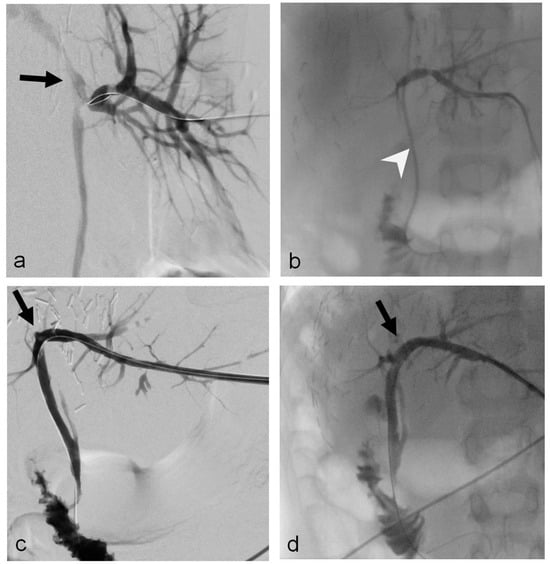

- Uller, W.; Wohlgemuth, W.A.; Hammer, S.; Knoppke, B.; Goessmann, H.; Loss, M.; Schlitt, H.J.; Stroszczynski, C.; Zorger, N.; Heiss, P. Percutaneous treatment of biliary complications in pediatric patients after liver transplantation. Rofo 2014, 186, 1127–1133. [Google Scholar] [CrossRef]